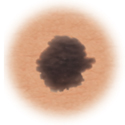

Melanoma

Color

When the color of the mole varies throughout